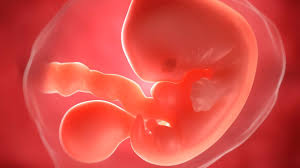

In dieser Woche kommt es bei Deinem Kind zum sogenannten physiologischen Nabelbruch und die Verknorpelung seiner zukünftigen Knochen beginnt. Schwangerschaftswoche der Embryo ist jetzt etwa sechs Wochen alt können Sie im Ultraschall erste Ansätze von Fingern und Zehen sehen. Dies sieht gewiss etwas unförmig aus wirkt aber zuckersüß.

Und wann macht der FA einen Bluttest bzgl. Der zweite Monat Deiner Schwangerschaft neigt sich dem Ende zu. Woche ist aus dem mikroskopisch kleinen Zellklümpchen ein 9 bis 16 Millimeter großer Minimensch geworden.

Alle inneren Organe sind angelegt und unter dem Gaumen bilden sich die Zahnanlagen. Schwangerschaftswoche ist Ihre erste Vorsorgeuntersuchung fällig. Der Dottersack ist ein wenig beachteter Nebenbefund beim Ultraschall in der Frühschwangerschaft. Bei der ersten von insgesamt 3 Ultraschall-Untersuchungen wird ein Bild des Embryos aufgenommen. Ultraschall beim führenden Marktplatz für Gebrauchtmaschinen kaufe. Er hat jetzt winzige Hände und Füße wobei sich die oberen Extremitäten etwas schneller entwickeln als. Woche ist aus dem mikroskopisch kleinen Zellklümpchen ein 9 bis 16 Millimeter großer Minimensch geworden. Die Ellbogen nehmen Form an und die Entwicklung der Finger beginnt an den Beinen sind Ansätze der Füße und sogar schon Zehen erkennbar. Da meine fa am Anfang der ss in Urlaub war bin ich parallel.